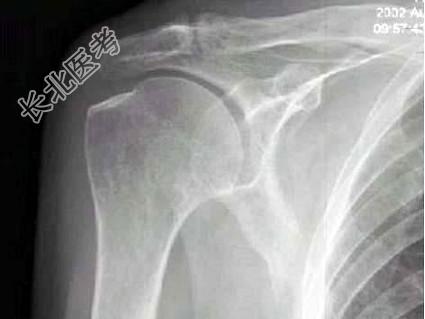

单项选择题右肩关节活动受限1年多,体检发现右手上抬不能, 后展受限,行右肩关节摄片如图示, 最可能的诊断是 ( )

A、正常右肩关节

B、右肱骨骨质疏松

C、右肩关节周围炎

D、右肩关节滑囊炎

E、右肩关节结核